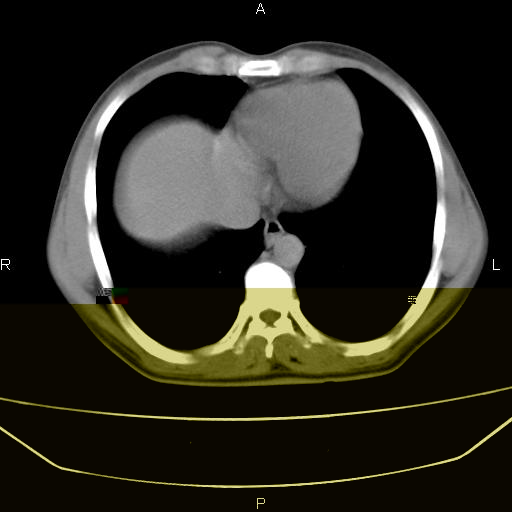

患者,男,40岁。间断发热,咳嗽二十余日。体温最高达38.9° 在当地诊所抗炎治疗三天后体温降至正常,患者自行停药。今又发热。胸片示,左下肺阴影。

左下肺片状高密度影,境界模糊,密度不均,考虑感染性病变可能性大,建议抗炎治疗后复查。左肺门增大,不除外占位性病变,必要时支气管镜检。